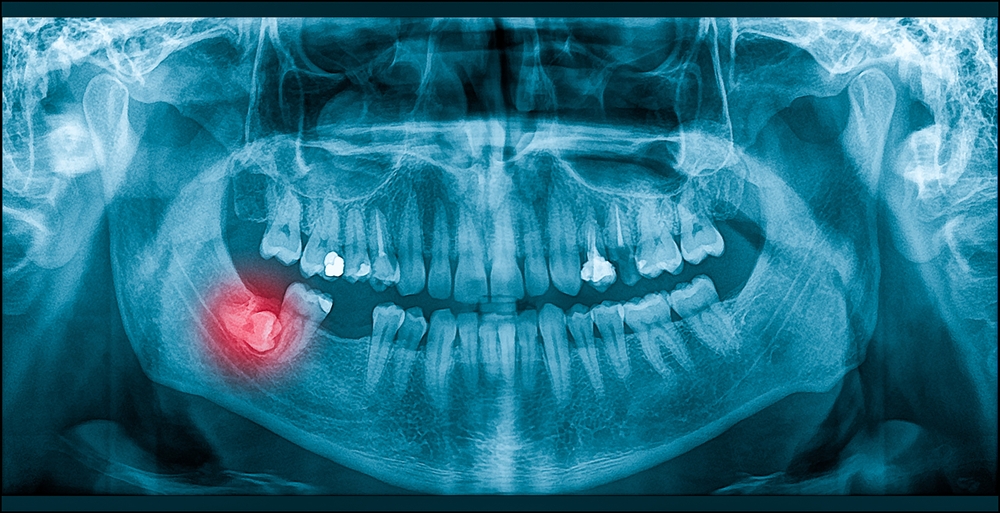

How imaging guides the decision

Panoramic X-rays give a broad view of tooth position and root development, while a cone beam CT (CBCT) offers 3D detail on root shape and the exact relationship to the inferior alveolar nerve. This imaging helps the surgeon plan a safe approach, determine whether extraction can be done in-office or in a hospital, and estimate the risks of recovery for wisdom teeth in Omaha, NE.